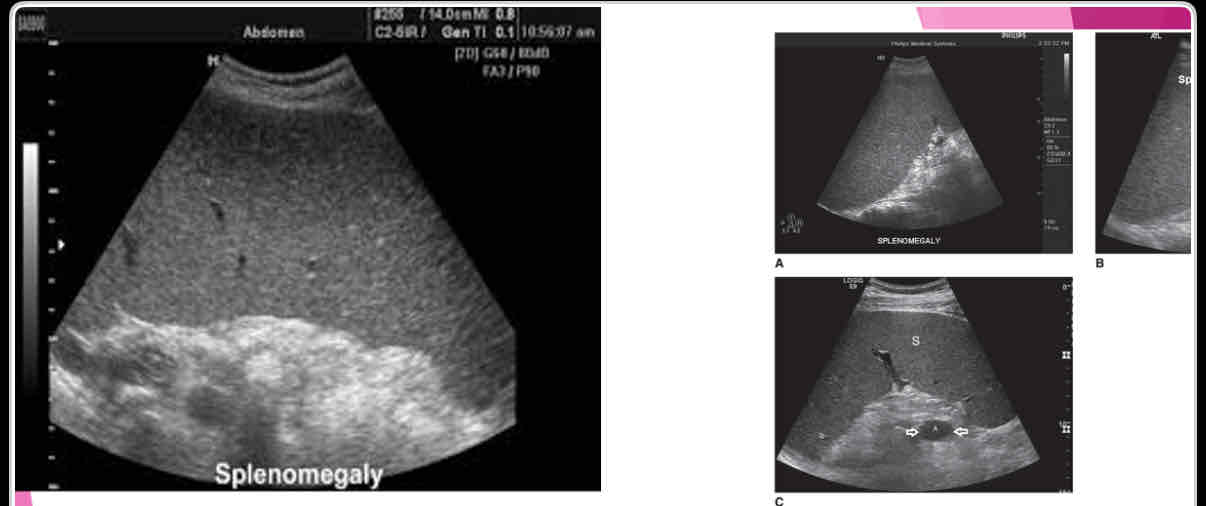

What is the measurement for enlarged spleen (splenomegaly)?

>13cm in length

What is the most common splenic abnormality observed sonographically?

enlargement (splenomegaly)

What is the most common cause of splenomegaly?

Portal hypertension due to cirrhosis is most common cause in adults

With splenomegaly: when enlarges, it extends

anteriorly, medially and inferiorly